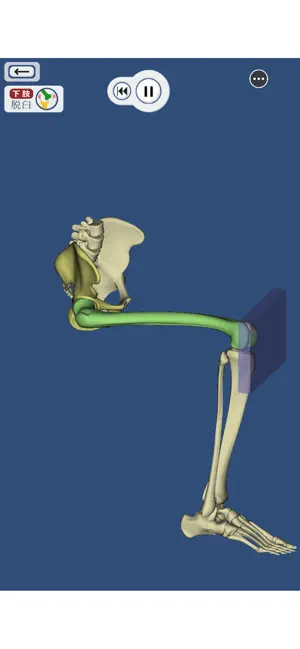

上肢、下肢の骨折と脱臼を3DCGのモデルとアニメーションで再現した骨折と脱臼を学ぶアプリ。

書籍や図譜では分かりにくかった骨折・脱臼の発生機転や転位が立体的に理解できます。

・上肢・下肢の骨折・脱臼を360°好きなアングルで!

・骨折・脱臼の発生機転をCGアニメーションで再現